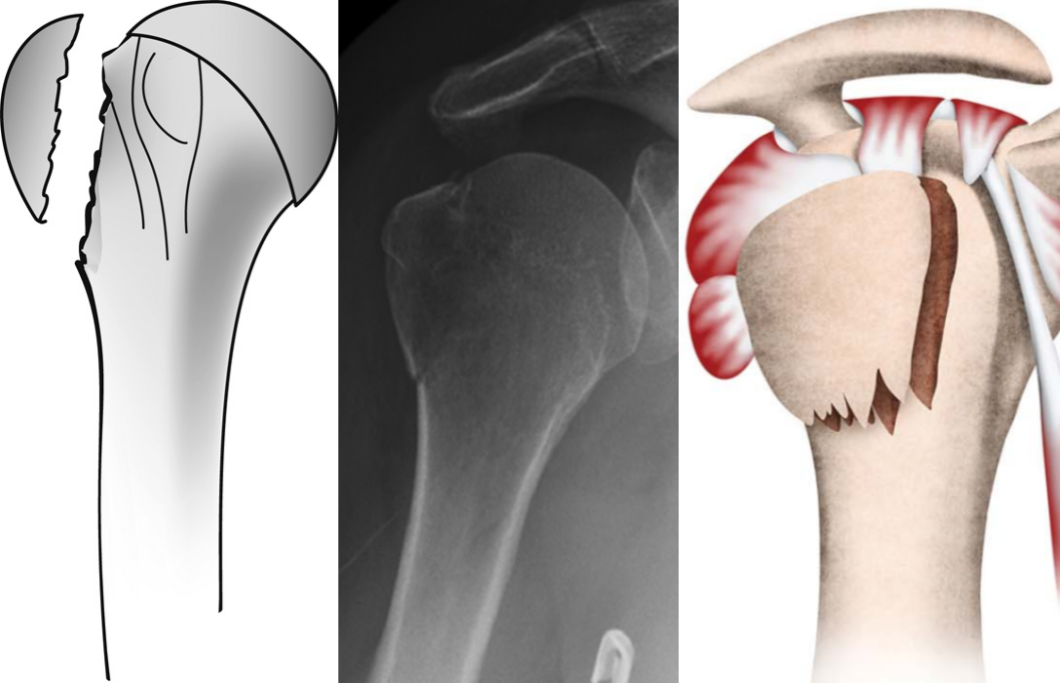

单纯大结节骨折移位较大甚至突入肱骨头及肩峰之间。

肱骨大结节骨折 ORIF,术前 X 线片显示肱骨大结节骨折情况;术中暴露肱

肱骨大结节骨折 ORIF,术前 X 线片显示肱骨大结节骨折情况;术中暴露肱